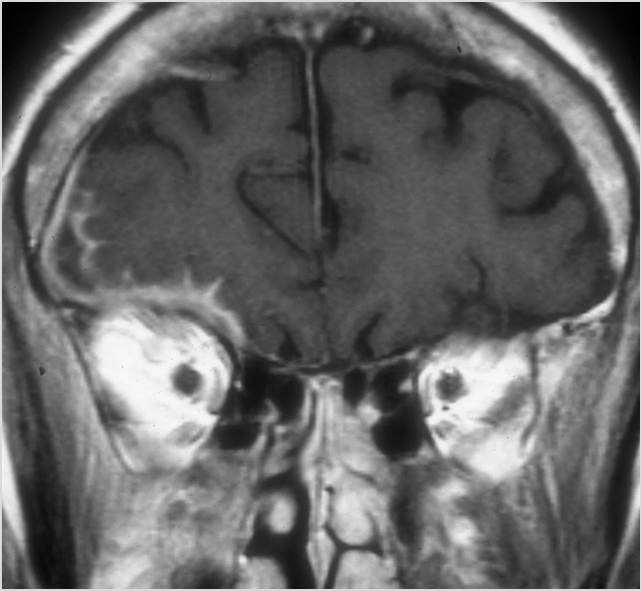

Orbits

The superior and/or inferior ophthalmic veins are dilated or thrombosed. [Yes/No]

Proptosis is present. [Yes/No]

The optic nerve is stretched in appearance. [Yes/No]

The posterior aspect of the globe is tented in appearance. [Yes/No]

There is evidence of thrombus, thrombophlebitis or other occlusive or inflammatory process of the cavernous sinus. [Yes/No]